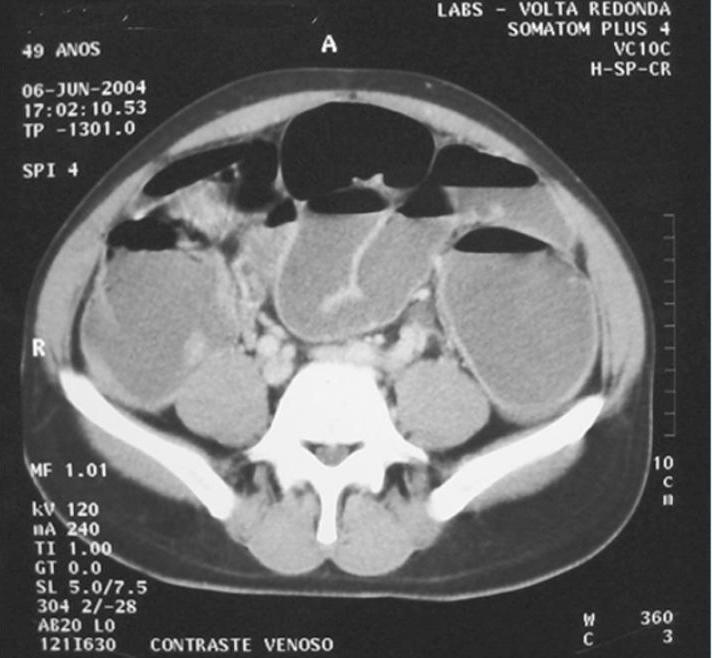

Obstrução Intestinal do Cólon

Large bowel obstruction

Caso Código 010B de Obstrução Intestinal do Cólon - Case Code 010B of Large bowel obstruction

Obstrução Neoplásica do Cólon.